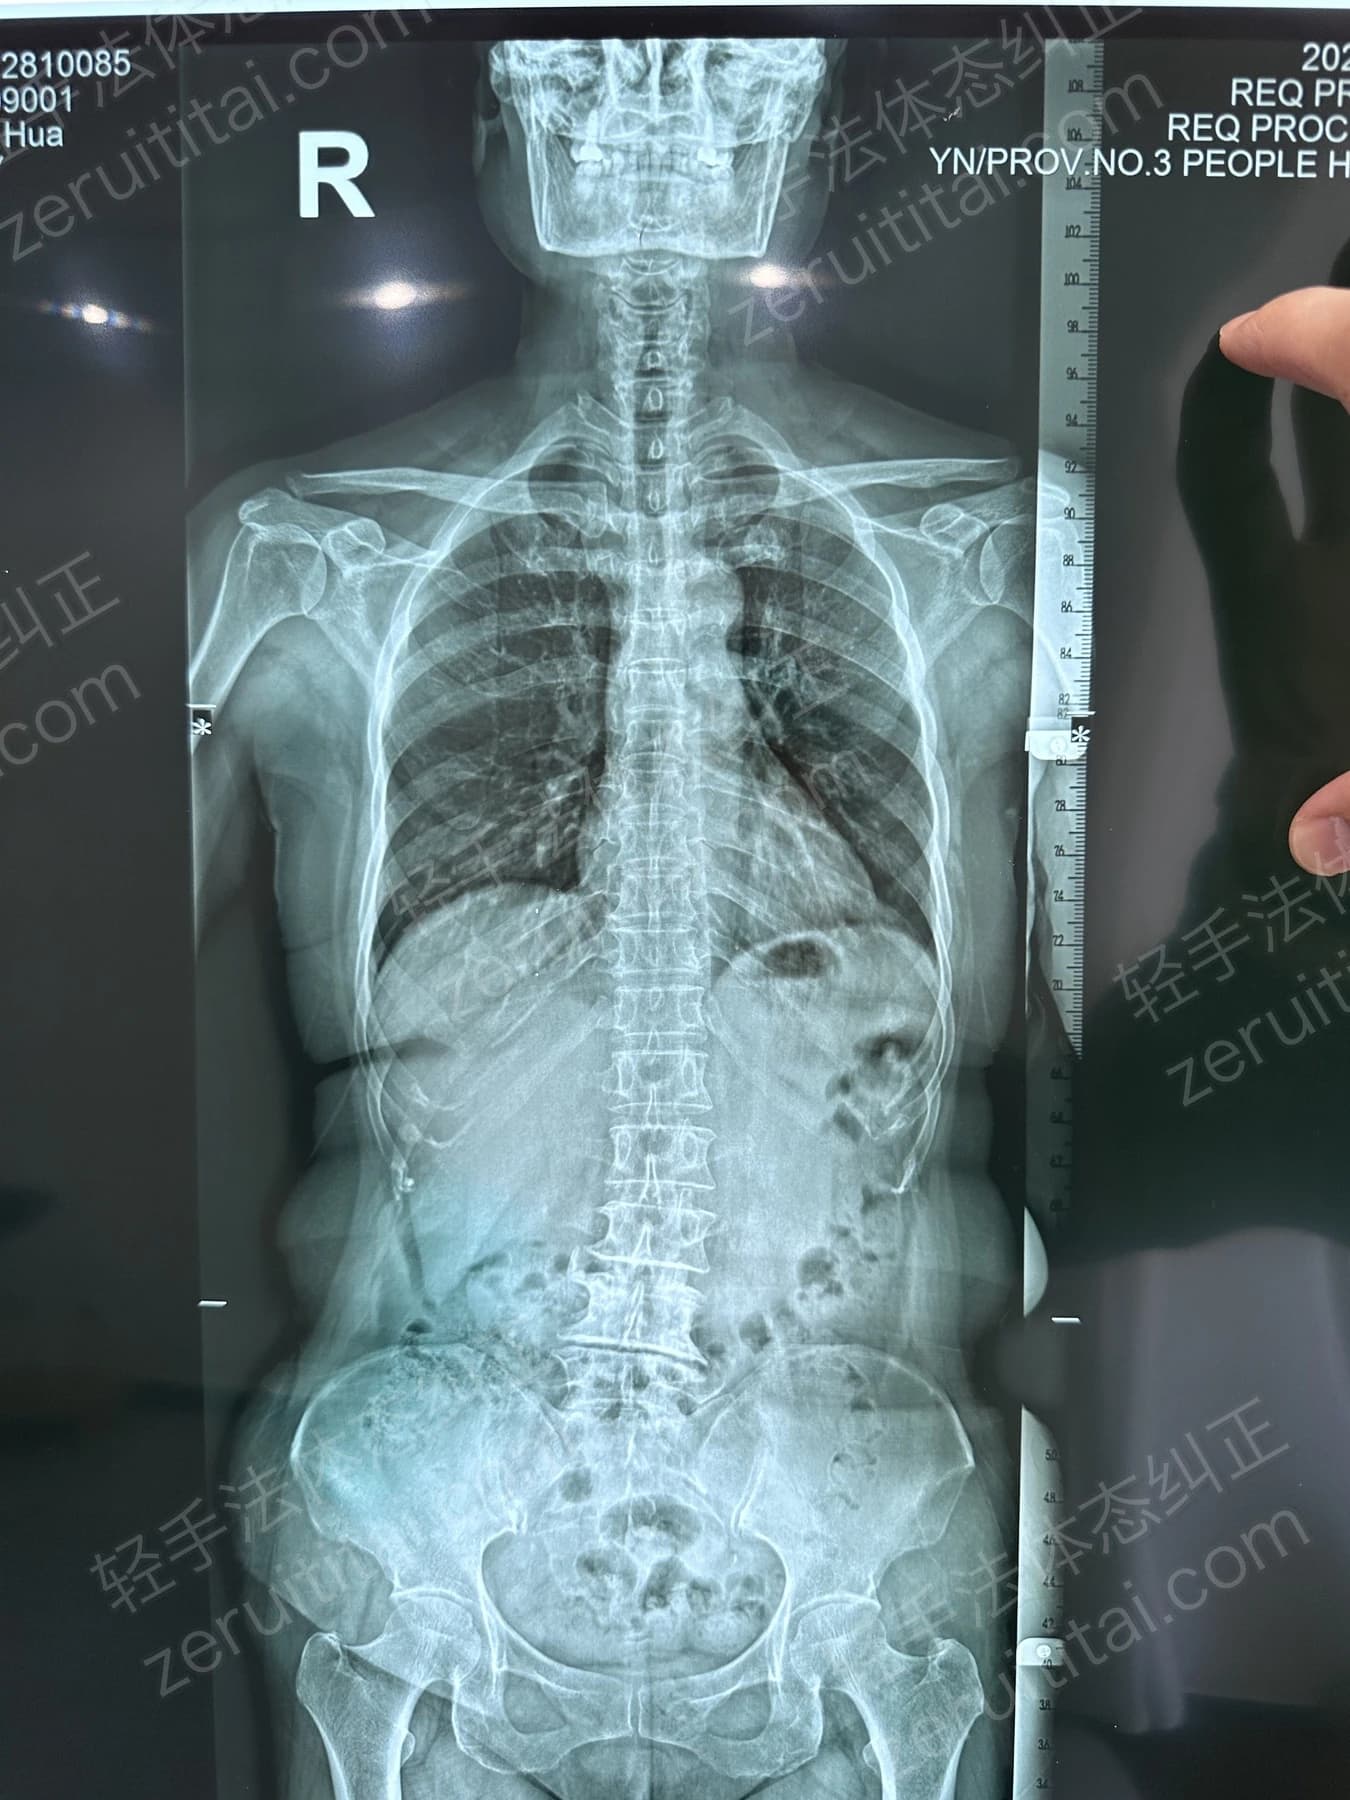

2022.09.27

第 2 次记录